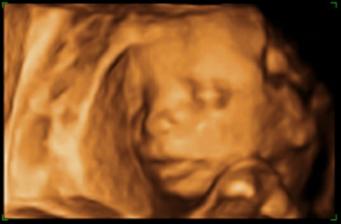

23.5. - 3D ultrazvuk - naozaj zážitok, už vieme, že čakáme druhého chlapčeka. Má 350g a 20cm bez nožičiek 🙂